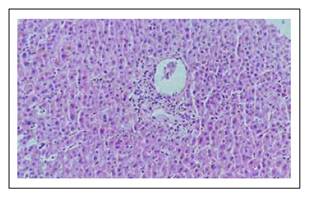

Los hallazgos histológicos en la biopsia hepática se muestran en las Figuras 1 a 6.

Figura 2 Los espacios porta mostraron leve infiltrado inflamatorio mixto a linfocitos, polimorfonucleares, que no rebasan la placa limitante. Uno de los 14 espacios porta de la biopsia muestra infiltrado inflamatorio mixto, leve, que no rebasa la placa limitante, en el acino se observan linfocitos y polinucleares. Se observa además linfocitos agrediendo el endotelio de la vénula de la microvasculatura portal.